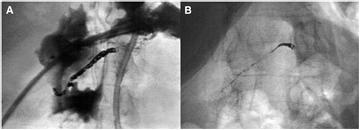

Barrett et al [66] demonstrated similar results for W MDS coils used for endovascular embolisation of varicoceles in the scrotum, presenting radiographic evidence of W resorption in 4 out of 18 patients (figure 3), and elevated W blood levels in 18 out of 19 patients (mean 40 months post-implantation). Bachthaler et al [60] reported W coil corrosion for intracerebral aneurysms and dural fistulae 26 months post-implantation in 9 out of 14 patients also by plain radiography, with two patients displaying complete coil resorption. W blood levels were elevated in 6 out of 14 patients, and urine levels were elevated in all. Others have reported similar radiographic and blood serum results with the use of W embolisation coils in intracranial aneurysms, abdominal aortic stent grafts, spermatic vein varioceles, oesophageal and gastric varices, and other pathological blood vessels (figures 4 and 5) [61, 67–70].

Standard image High-resolution imageFigure 4. W coil embolisation of the right hepatic artery for massive haemorrhage after stomach resection. (A) Image obtained immediately post-procedure; (B) 35 months later, with clear decrease in metal density [60].